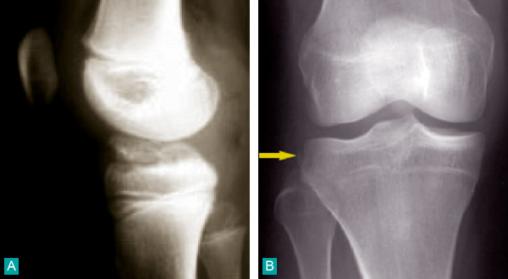

Lésions osseuses radiologiques d'une rupture du ligament croisé antérieur

A. Profil : avulsion du massif des épines tibiales.B. Face : fracture de Segond.